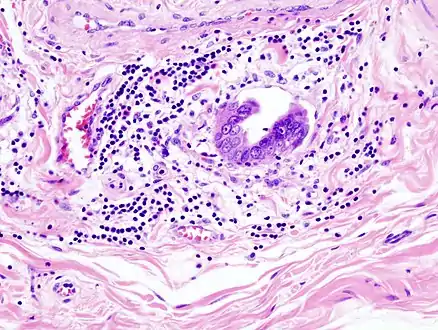

Gallbladder adenocarcinoma histopathology